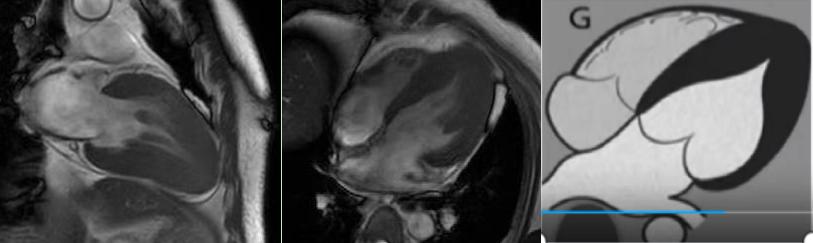

肥厚型心肌病,舒張末期心尖形似“黑桃A征”